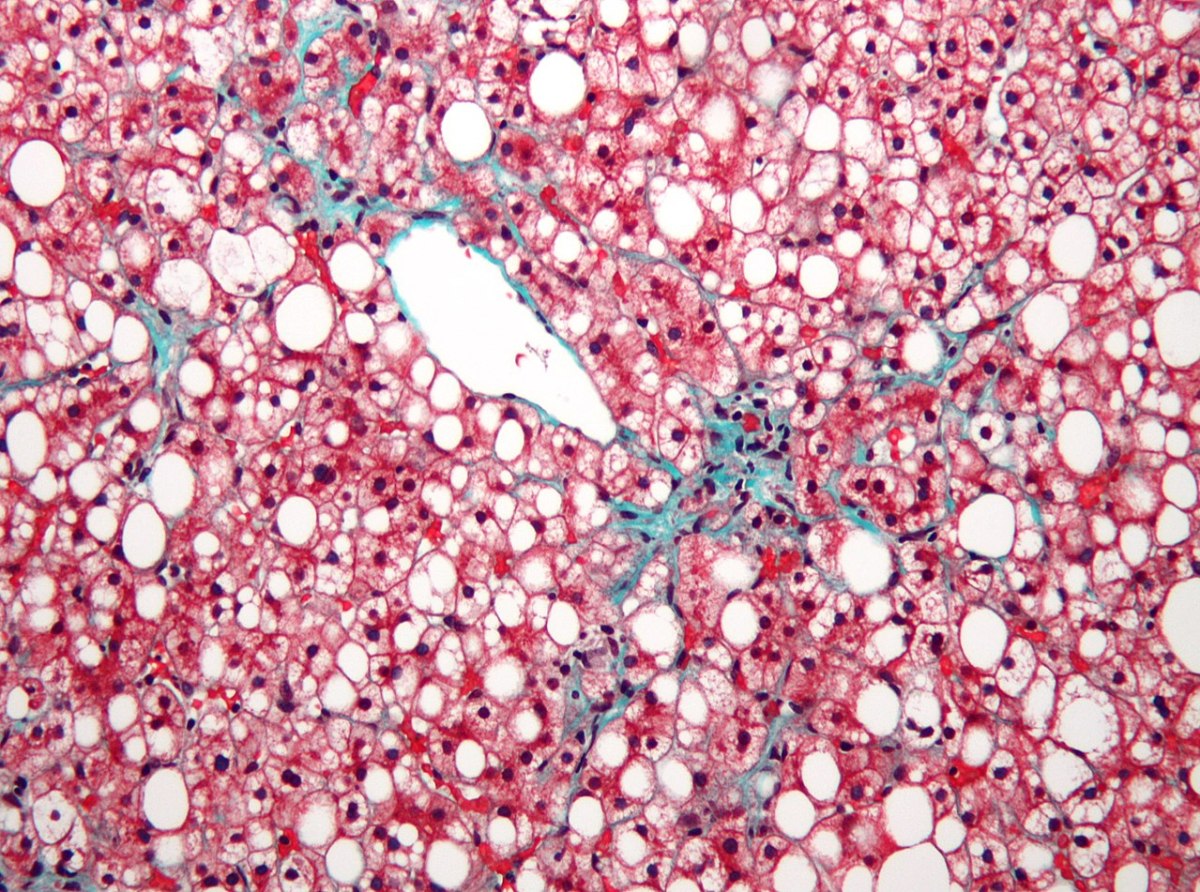

Η MASLD η οποία μέχρι προσφάτως ονομαζόταν μη αλκοολική λιπώδης νόσος του ήπατος αφορά συσσώρευση περιττού λίπους στο ήπαρ. Μακροπρόθεσμα η κατάσταση αυτή μπορεί να πυροδοτήσει φλεγμονή (ηπατίτιδα) και να εκδηλωθεί με συμπτώματα όπως οι πόνοι στην κοιλιακή χώρα, η κόπωση και η απώλεια της όρεξης. Η MASDL αποτελεί την πιο κοινή χρόνια ηπατική πάθηση παγκοσμίως πλήττοντας ποσοστό μεγαλύτερο του 30% του πληθυσμού ενώ μετατρέπεται ταχέως σε κύρια αιτία θανάτου από ηπατικά αίτια.